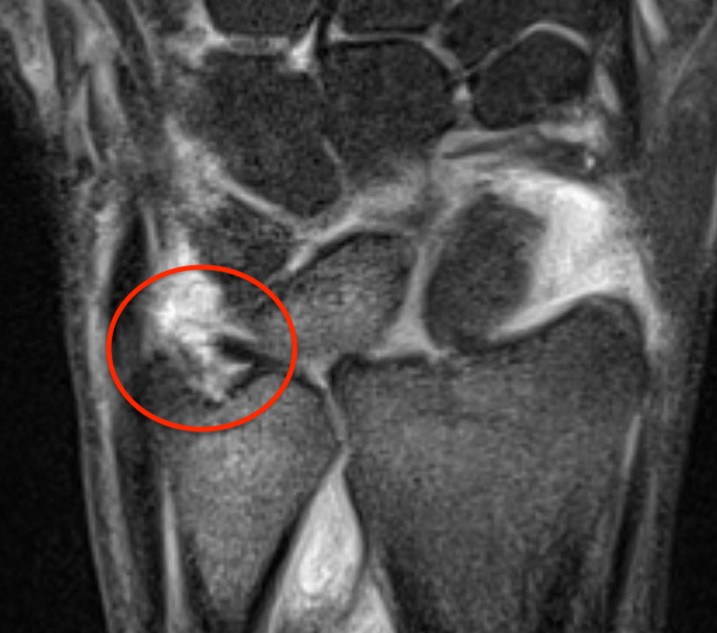

TFCC tears

Ulna sided tear